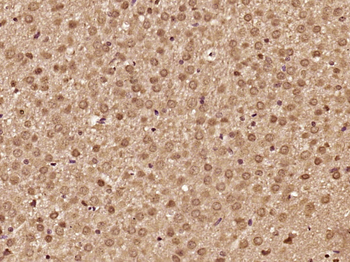

100 μl, 200 μl, 50 μlSMAD7 Rabbit Polyclonal Antibody [orb500819]

FC, ICC, IF, IHC-Fr, IHC-P, WB

Bovine, Porcine

Human, Mouse, Rat

Rabbit

Polyclonal

Unconjugated

100 μl, 200 μl, 50 μlPhospho-Smad3 (Ser213) Rabbit Polyclonal Antibody [orb106193]